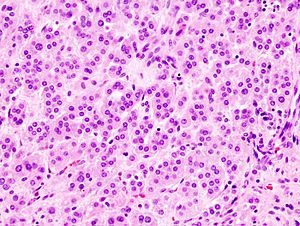

Adrenal cortical adenoma. H&E stain. | |

Microscopic

Classic features:

- Well-defined cell borders.

- Clear cells (abundant, finely vacuolated cytoplasm)

- Polygonal pink cells.

- Most of the nuclei are bland, central and round.

- May have foci of necrosis/degeneration and nuclear atypia.